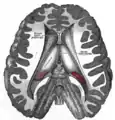

غده کاجی یا غده اپیفیز (به انگلیسی: epiphysis gland) یا غده پینهآل (به انگلیسی: pineal gland) یا غده صنوبری که غده رومغزی هم نامیده شده و به چشم سوم نیز معروف است تودهٔ بافتی مخروطیشکل کوچکی است که به وسیلهٔ ساقهای به سقف بطن سوم مغز متصل است. این غده درونریز است و متشکل از سلولهای پینهآل و بینابینی میباشد و در عمق مغز (دیانسفال) و در بین دو نیمکره چپ و راست مخ قرار دارد. کارکرد دقیق آن هنوز مشخص نیست، البته این غده هورمونی به نام ملاتونین و ماده شیمیایی به نام سروتونین را ترشح میکند که ترشح این هورمونها در شب به حداکثر و در نزدیکی ظهر به حداقل خود میرسد. همچنین با چرخه روزانه خواب و بیداری مرتبط میباشد. به علاوه در این غده گیرندههای مواد مخدر (انواع خاصی از مشتقات آمفتامینها) وجود دارد. برای حفاظت از این غده باید آب قلیایی یا مقطر نوشید

جسم کاجی یک تودهٔ غیر عصبی مخروطی شکل است که در بالای Colliculusهای بالایی قرار دارد و به وسیلهٔ پایهٔ باریک خود به قسمت پایین سطح خلفی دیانسفالون چسبیدهاست. انشعابی از بطن سوم به نام pineal recess با این پایه وارد میشود و آن را به دو ورقه تقسیم میکند. ورقهٔ بالایی را رابط هابنولار(Habenular Commissure) و ورقهٔ پایینی را رابط خلفی(Posterior Commissure) مینامند. جسم پینه آل بعد از بلوغ آهکی میگردد.